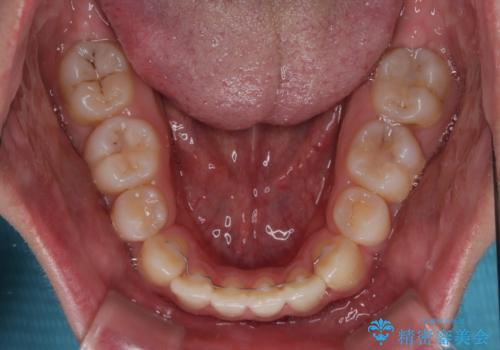

- 前歯のデコボコと口元の突出感を気にして来院された患者様です。

上下前歯がくちばしのように突出していたため、上下左右の第一小臼歯4本を抜歯し、ワイヤー装置にて矯正治療を行うこととしました。

左上は第二小臼歯が90度捻れており、状態が良くない歯であったため、左のみ第二小臼歯を抜歯することとしました。

第二小臼歯抜歯により治療期間が長くなることを了承いただき、治療を開始しました。

上顎骨に対して下顎骨がやや前方位に位置しているため、下顎前歯をあまり内側に移動させることができず、口元の突出感改善は期待以上にはならないと予測しておりましたが、満足いくの引っ込み具合となりました。